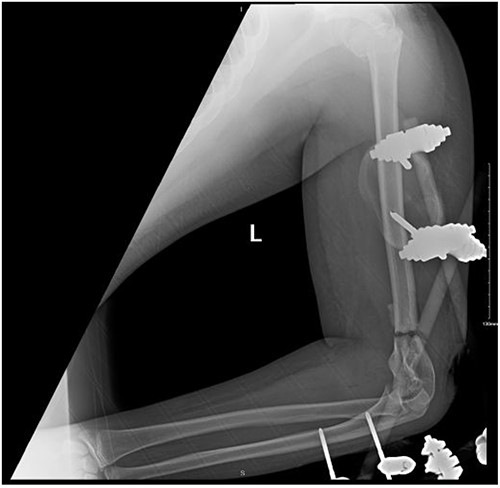

Upon arrival the patient underwent exploratory laparotomy followed by irrigation and debridement of both femur and humerus and application of external fixators (Fig. 2). The patient was admitted to the intensive care unit (ICU). Two days later, the patient underwent open reduction and internal fixation of both proximal and distal humerus (Fig. 3).

Anteroposterior (AP) view of the left humerus and elbow after ORIF.

The patient underwent left open reduction and internal fixation of proximal and distal humerus under general anesthesia. The patient was placed in the lateral position. Preparation and draping in the usual sterile manner were performed and a sterile tourniquet was used. The distal humerus was first approached through a posterior approach. Ulnar nerve protection and olecranon osteotomy was done, showing simple distal intraarticular fracture with minimal metaphyseal comminution. Anatomical reduction of the articular fracture was achieved, with preliminary fixation by k-wires holding the intra-articular fragments. This was followed by interfragmentary screw fixation from medial to lateral. Dual plate fixation (posterolateral and medial anatomical plates) was used to fix both medial and lateral columns, connecting the articular fragment to the metaphyseal. Reduction was confirmed under x-ray. Joint was tested for any screw penetration, and none was found. The osteotomized olecranon was reduced and fixed with cannulated screws and tension bands. The ulnar nerve was protected throughout the whole procedure and was reduced back into the cubital tunnel. Range of motion was examined; full range of motion was achieved. Finally, closure was done in layers.

The patient was then shifted from lateral to beach-chair position, and preparation and draping were repeated. A deltopectoral approach was utilized reaching to the proximal humerus. Reduction was achieved, followed by preliminary fixation with k-wires. Philos plates were used to fix the fracture. Range of motion was examined afterward, with no struggles detected. Fluoroscopic images were taken later to make sure no screws had penetrated the joint. Closure in layers was done, followed by dressing and application of an arm sling.